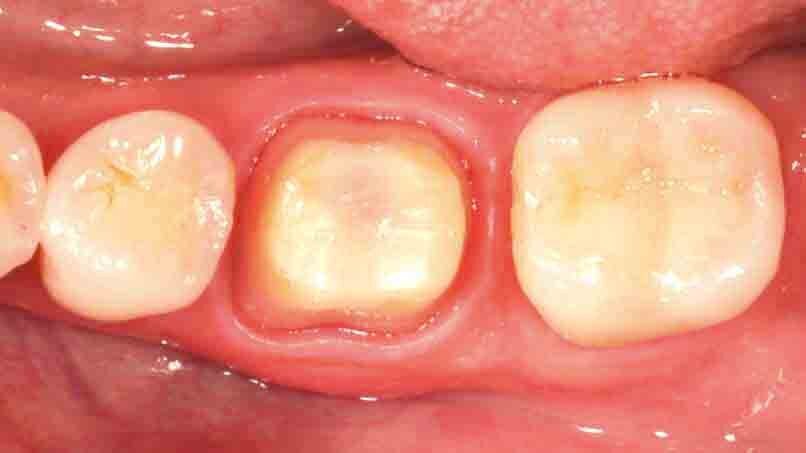

Fig. 1: Initial situation. The failed composite restoration covering a large part of the left mandibular first molar’s occlusal surface needs to be replaced.

Fig. 2: Due to the size of the restoration, the amount of remaining tooth structure might not be sufficient to ensure the required stability for a direct composite restoration.